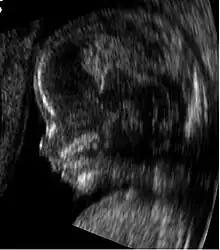

Profil d'un fœtus de 14 semaines

Tubercule génital chez un fœtus de 14 semaines. L'orientation indique qu'il s'agit d'une vulve en formation.

La détermination précoce se fait sur l'orientation du tubercule génital de l'embryon sur une coupe sagittale stricte de l'embryon. Cette formation embryonnaire est l'origine commune des organes génitaux externes ou internes.

Cette détermination se fait en mesurant l'angle du tubercule génital par rapport à une ligne horizontale passant par le revêtement cutané de la région lombaire (le bas du dos). L'embryon est masculin si l'angle est supérieur à 30 degrés. L'embryon est féminin si l'angle est inférieur à 10 degrés. Entre les deux la détermination du sexe est impossible. De façon plus rapide : lorsque le tubercule génital est orienté vers l'arrière, il s'agit d'un embryon femelle. En cas d'orientation vers l'avant, il s'agit d'un embryon mâle.